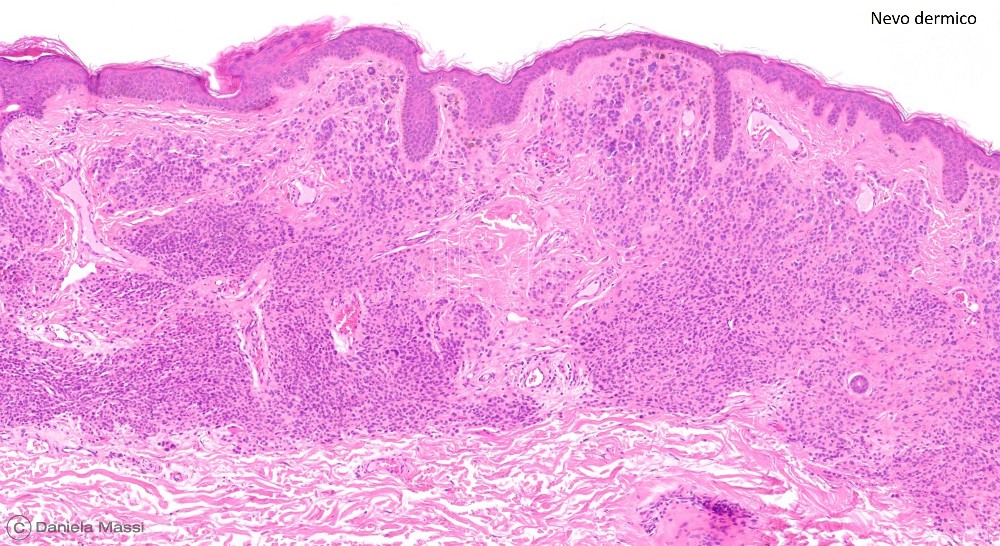

I nevi più comuni sono classificati istologicamente a seconda della loro prevalente localizzazione in relazione alla cute in: